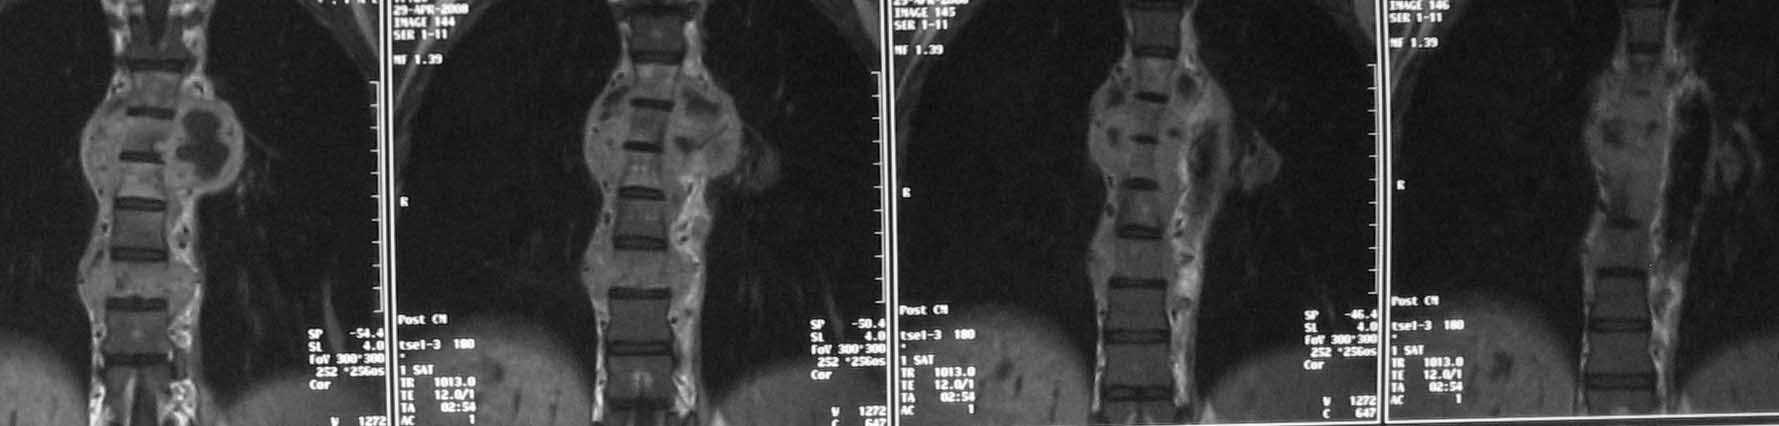

Случай действительно не стандартный и по результататам операционной ревизии обойтись без первичной иснрументации не удалось. первым этапом выполнена задняя ТПФ, вторым - левосторонняя торакотомия (соответственно максимальным изменениям паравертебральных тканей). при ревизии выявлено, что "жидкого" гноя нет, позвонки окружены гнойными вялыми, практически не кровоточащими грануляциями, тела позвонков Т5-9, включая 8 представляют собой "медовые соты ", фрагменты тел позвонков легко удаляются даже пинцетом. спинной мозг также сдавлен гнойными грануляциями. Тела Т5-9 удалены полностью. Установлен пористый никелид титана, обильно "сдобренный" цефобидом. Проточно-промывное дренирование.

spondylodiscit 6.jpg